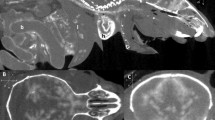

a The postoperative CT image co-registered with the high signal-to-noise ratio (SNR) T1-weighted preoperative MRI image shows the hippocampus (white dashed box) in addition to the ventricles (blue arrows). The yellow arrow shows the position of an edge silicon probe in the hippocampus. Images from left to right, maximum intensity projection, sagittal slice, horizontal slice, and coronal slice. Yellow numbers refer to the corresponding stereotaxic coordinates in mm relative to Bregma. b Three-dimensional atlas co-registered with the postoperative CT image using the CT–MRI fusion technique with special attention to the alignment of the hippocampal structure. c Left, localized trajectory of the probe in the hippocampus. Right, layer-specific reconstruction of 32 contact sites (Or oriens layer, Py pyramidal layer, Rad stratum radiatum, LMol lacunosum moleculare, Mol molecular layer, GrDG granular layer, PoDG polymorph layer, DG dentate gyrus). CT and MRI images are shown in grayscale and goldscale, respectively.

To test this, we implanted the dorsal hippocampus (n = 3, two mice with silicon probes, one with a 105-µm core optic fiber) and took high SNR T1-weighted preoperative MRI images in addition to the previously described pre- and postoperative CT images (Fig. 5a). By visualizing the hippocampal formation in addition to the ventricles, these images allowed registration to the MRI atlas (step (iii) above) paying special attention to the area around the implant (Fig. 5b and Supplementary Fig. 3). As a result, we were able to precisely localize the implant’s trajectory in the hippocampus; for silicon probe implants, this also allowed us to reconstruct the layer-specific position of each contact site based on its nominal distances from the implant tip (Fig. 5c). Localizing the trajectory might also allow the precise adjustment of the probe with suitable microdrives33.